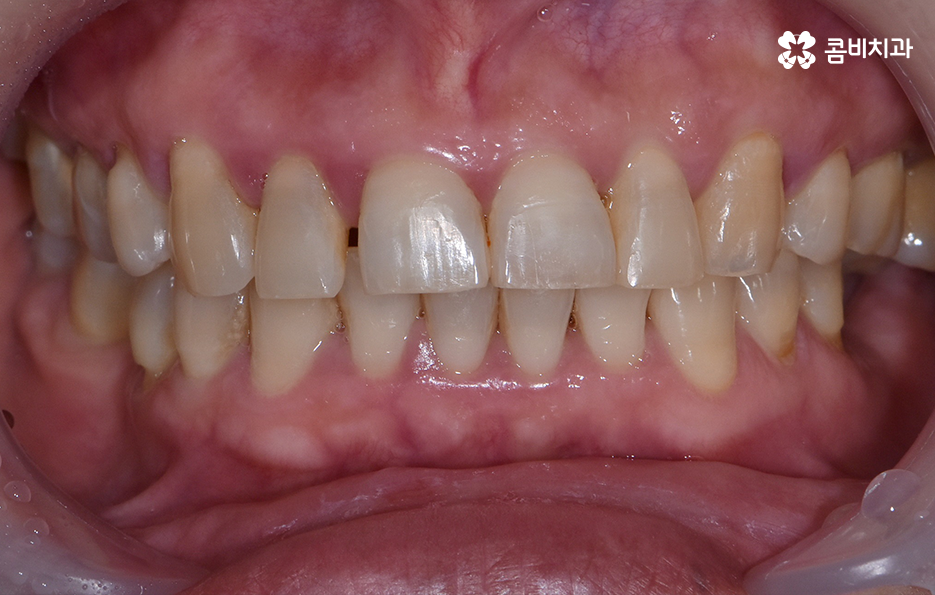

오늘 보시는 포스팅에서의 치료 과정도 어금니에 임플란트가 필요한 상태에서 윗니를 보시면 윗니가 다소 벌어진 것을 확인할 수 있는데요. 교정 하면 보통 전체교정을 떠올리게 되긴 하지만 경우에 따라서는 치열이 전체적으로 가지런한 편인데 앞니가 살짝 벌어진 경우나 어금니만 다소 벌어진 경우도 있을 거예요

이러한 경우에는 부분교정을 통해서 다소 개선이 필요한 치열을 가지런하게 만들고 가지런해진 치열과 교합 상태에 적합한 임플란트 치료 계획을 세워서 치아의 심미성과 기능적인 부분, 얼굴과의 조화를 종합적으로 고려하여 좋은 결과를 얻을 수 있어요